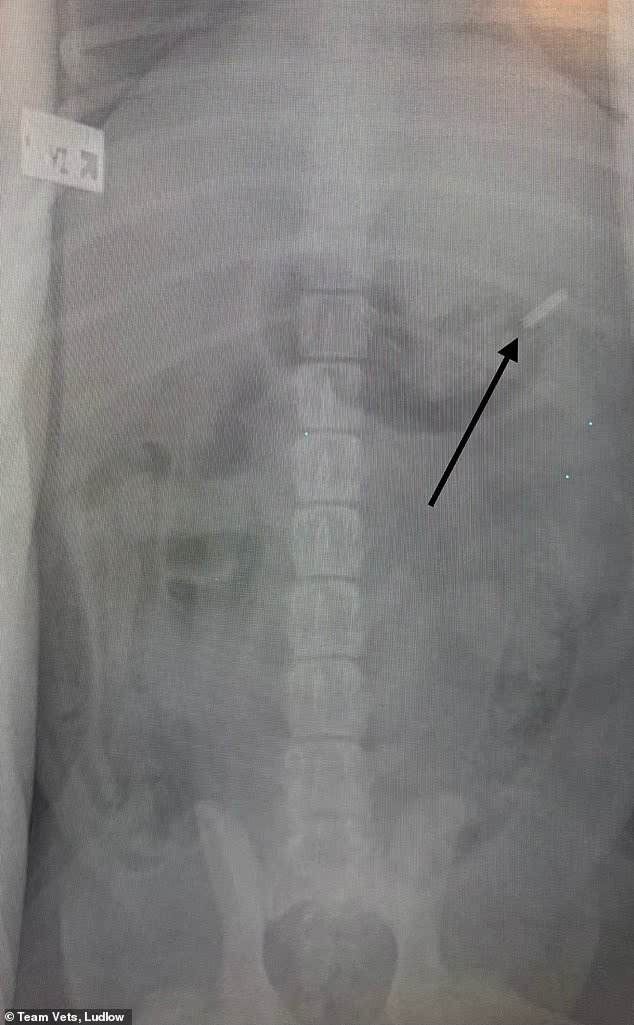

Charlie pasó por el quirófano después de que una radiografía confirmara que la cuchilla de 39 mm (1,5 pulgadas) estaba alojada en su estómago y regresó a casa ese mismo día después de una cirugía de emergencia para extraer el objeto.

Una radiografía confirmó que la cuchilla de 39 mm (1,5 pulgadas) estaba alojada en el estómago de Charlie.

‘A la mañana siguiente lo acogimos y los rayos X confirmaron nuestros temores de que se hubiera tragado la hoja de afeitar.